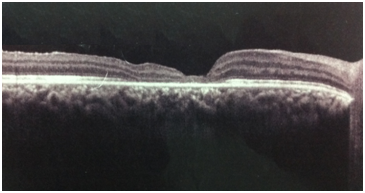

A 43-year-old male patient with a history of trauma with fireworks in the OD 8 months ago, with LVA and "dark spot in vision" since then. Denies previous ophthalmological comorbidities. At ophthalmologic examination: visual acuity of 20/200 in OD and 20/20 in OS. Biomicroscopy showing posterior subcapsular cataract in OD and without abnormalities in OS. 10 and 14mmHg aplanation tonometry in OD and OS, respectively. Funduscopy presented with macular hole and choroidal rupture in OD and without abnormality in OS (Figure 3). OCT examination of the macular region of the patient right eye (Figure 4) confirmed the fundoscopic finding.

Figure 4 Preoperative OCT presenting with a macular hole.